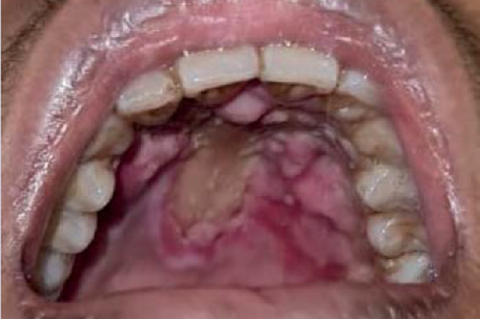

Atypical Manifestation of Oral Candidiasis in Patient with Aplastic Anemia

Praf Nahlalogi,

Pharmacognosy Journal,16(5):1143-1149

DOI: 10.5530/pj.2024.16.187

Published: Wed, 30-Oct-2024